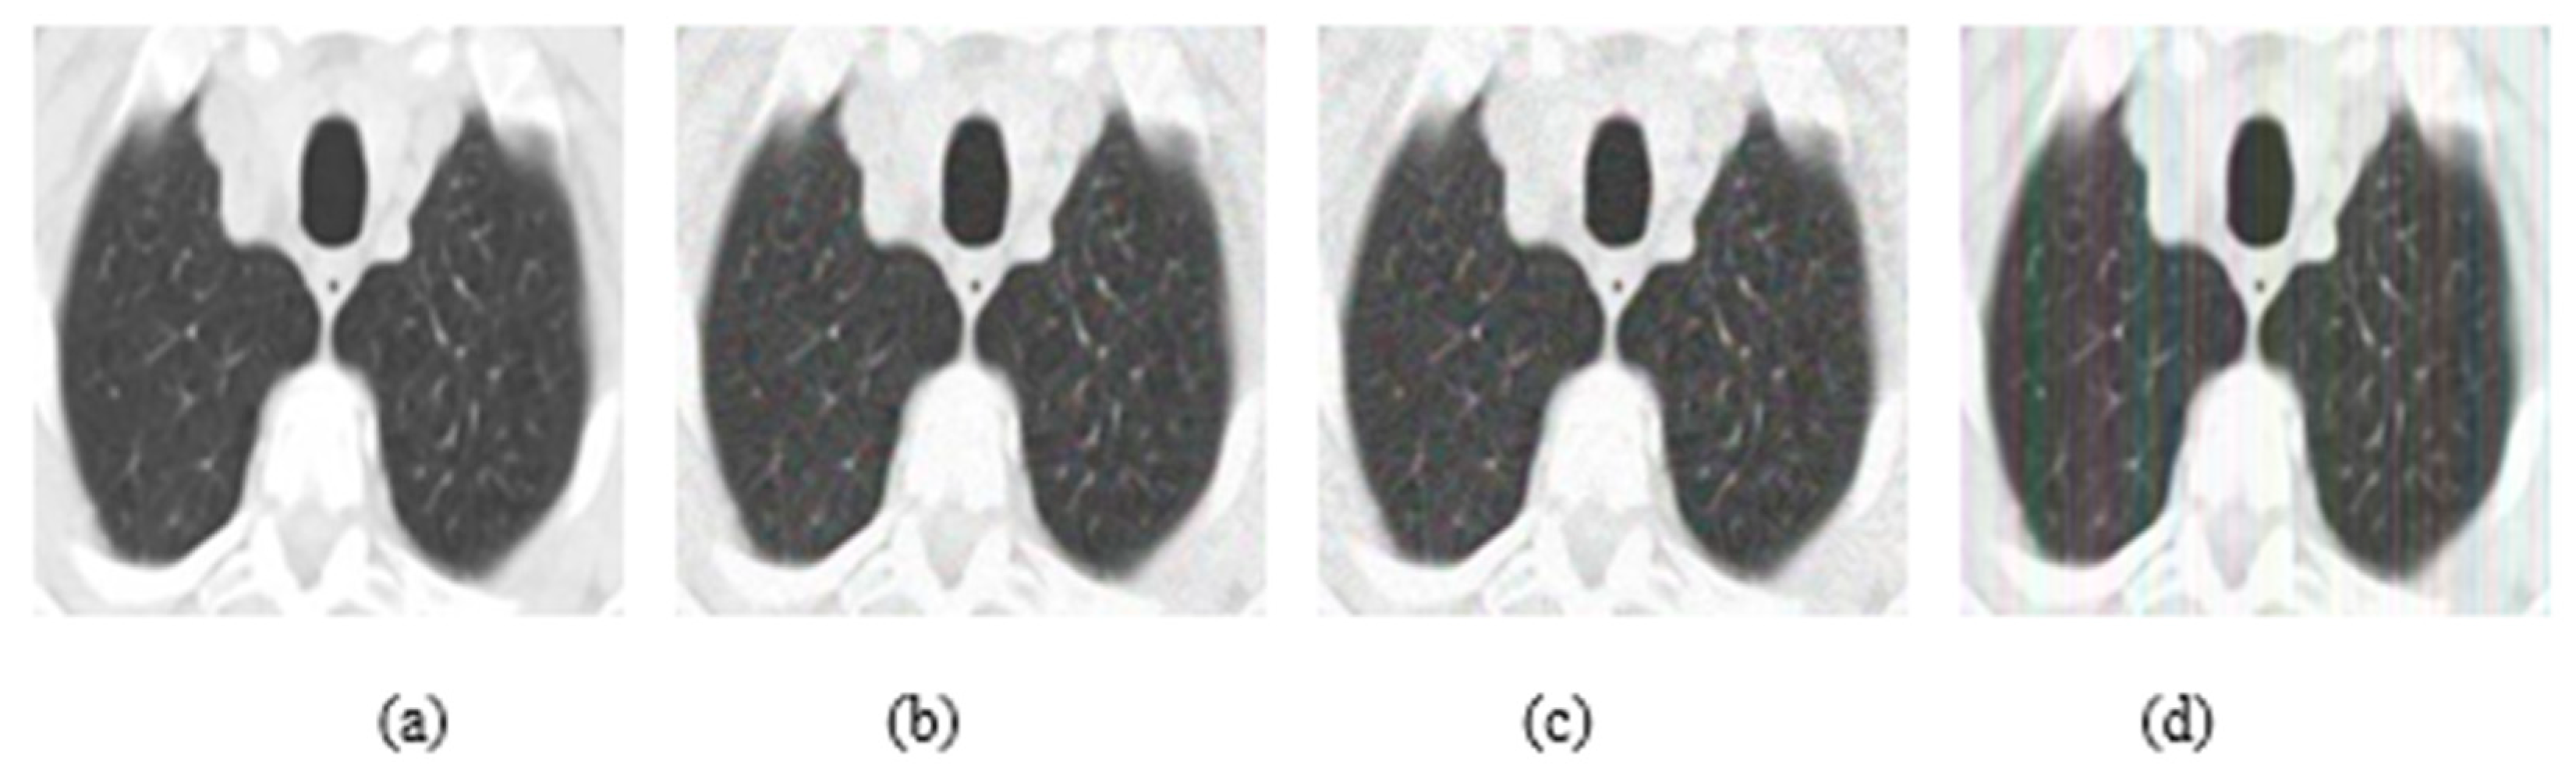

4.1. Datasets

4.2. Ablation Study

4.3. Results